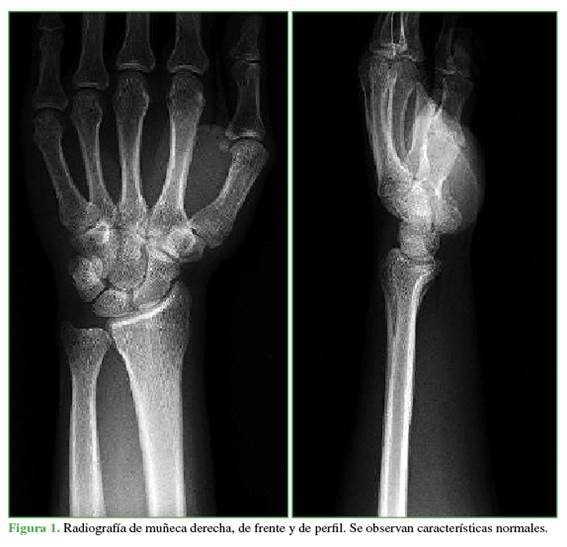

Durante el examen físico, no se palpan tumoraciones. No hay alteraciones de los pulsos en las maniobras dinámicas. Se detecta dolor a la compresión de los tendones flexores y signo de Tinel positivo. Se solicitan radiografías de muñeca derecha de frente y de perfil (Figura 1) y una ecografía de muñeca derecha (Figura 2).

HALLAZGOS e interpretación de los estudios por imágenes

La radiografía de muñeca (Figura 1) no muestra alteraciones. En la ecografía de muñeca derecha (Figura 2), se visualiza un nervio mediano de morfología bífida, con una tumoración que lo separa, redondeada, hipoecogénico sin flujo en el examen Doppler. No se observan alteraciones en los nervios radial ni cubital. Los tendones flexores y extensores tienen características normales. No hay derrame articular.